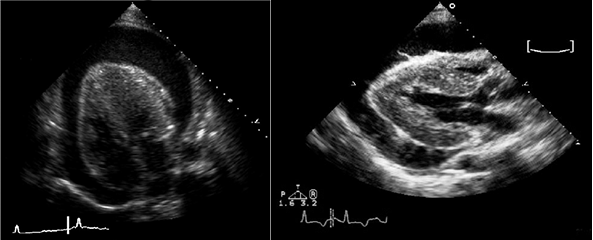

• Эхокардиография: выпот, утолщение перикарда.

• Выпот (>15–35 мл), сепарация эпикарда и перикарда >1 мм в диастолу.

• Величина выпота: малый (сепарация • Утолщение (>3–4 мм) и кальцификация перикарда (констриктивный перикардит).

• Эхокардиография: колебания сердца, выраженный выпот (>20 мм), диастолический коллапс камер сердца, аномальное движение МЖП, > вариабельности митрального потока (>25%) на вдохе.

- Эхокардиография: ЭхоКГ позволяет не только «увидеть» воспалительный процесс, но и измерить количество жидкости в полости перикарда. Это особенно важно для определения необходимости хирургического вмешательства – пункции перикарда с последующим удалением лишней жидкости.